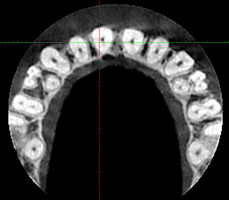

При анализе и описании компьютерной конусно-лучевой томографии (рис. 2а-г) была выявлена генерализованная первичная дегисценция вестибулярной пластинки кости от 1/2 до 3/4 длины корней зубов, зубной ряд целостный, все зубы витальны, кариозных поражений нет. Тип кости 1-2 (Lechkolm и Zarb, 1983), первичная дегисценция вестибулярной костной пластинки превышает пределы возрастной атрофии.

Через 12 месяцев (рис. 7а-г) на срезах компьютерной томограммы 11-ый и 13-ый зубы находятся в костной ткани, при этом костные пики и перегородки укрепились, объем их увеличился; вестибулярно заметен объем костной массы, предположительно компактной формации, исходя из электронной плотности участка. Этим объясняется отсутствие рецидива при лечении рецессии десны как в случае применения аутотрансплантата, также и ТМО (dura mater).